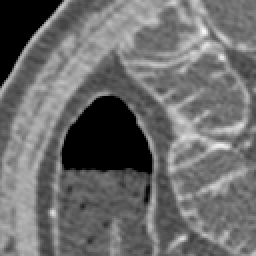

Elimination of noise in ultra low dose CT data

original section